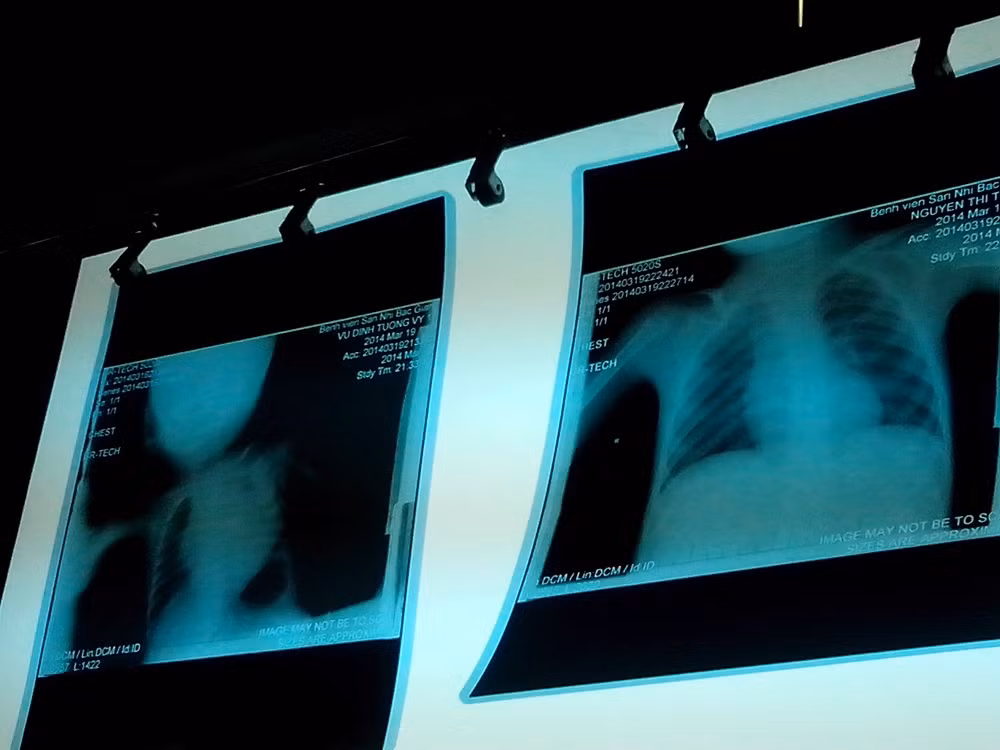

| BS. Nguyễn Văn Hùng đang chiếu lại phim chụp tim của bệnh nhi Vũ Đinh Tường Vi |

| Phim chụp tim của bệnh nhi Vi (bên trái) có hình ảnh tim to hơn bình thường |

Riêng đối với việc tiếp nhận và cấp cứu bệnh nhi Vũ Đình Tường Vi, BS. Nguyễn Đình Hùng, Phó giám đốc Bệnh viện Sản Nhi Bắc Giang cho biết: “Bệnh nhi được chuyển lên từ Bệnh viện huyện Lục Nam, với chẩn đoán suy hô hấp cấp độ II, còn tại bệnh viện Sản nhi, kết quả chẩn đoán vào lúc 19h45 phút cho thấy, bệnh nhi bị truỵ tim mạch, suy hô hấp cấp độ III”.

Ông Hùng cho biết thêm, sau khi có kết quả xét nghiệm và chụp Xquang, các bác sĩ đã kết luận bệnh nhân có dấu hiệu tim bẩm sinh, chỉ số tim ngực là 80% và thiếu máu (huyết sắc tố giảm 75g/l, Hematocrit 23%). Kết quả này đã được người nhà bệnh nhân trực tiếp xem và các bác sĩ cũng đã giải thích về tình trạng bệnh lý.